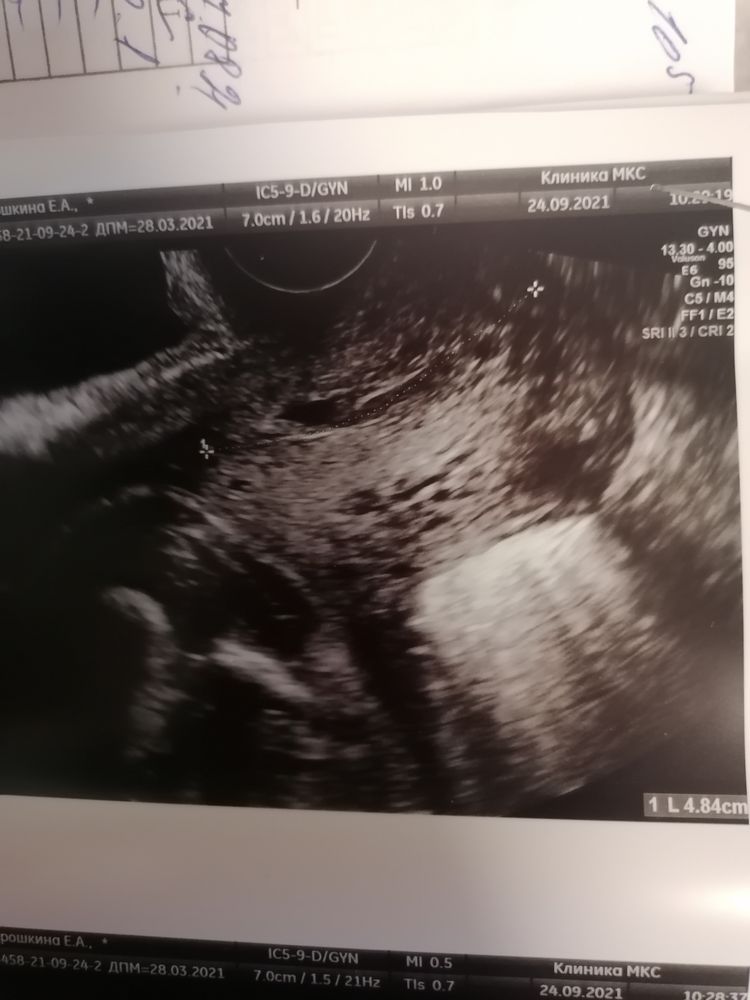

Помчалась на цирвикометрию. Шейка длинющая 45мм,зевы закрыты, но в 1/3 анэхогенное аваскулярное образование небольшое. Врач моя сказала, что на полип не похоже, скорее жидкость или слизь, мол ничего страшного, но я ж не могу не волноваться теперь. Через 10 дней посмотрим в динамике. Кто сталкивался? Что за новинка? Есть повод для беспокойства?

Тёмное пятно над шейкой или в самой шейке 🤷♀️